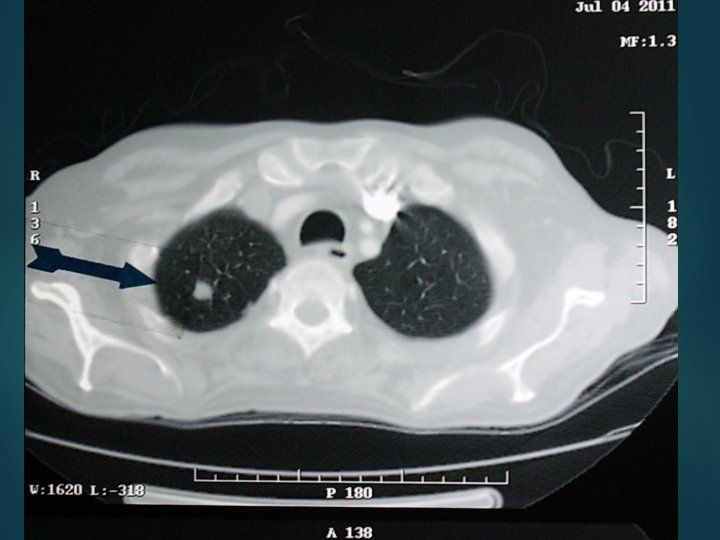

The 66 year old man was hospitalized because of asthenia, muscle weakness and 10 kg weight loss. Laboratory evaluation revealed, anemia, sever hypokalemia, hypercortisolism and metabolic alkalosis. Imaging showed multiple small lesions in lung and liver

Patient’s condition deteriorated very soon and expired after one week. Diagnosis was small cell carcinoma of unknown origin with lung and liver metastasis approved by bone marrow biopsy.